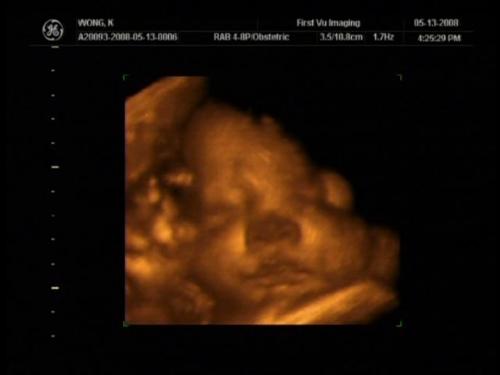

This is at 39wks Image Attachment(s):

Message edited 3/10/2010 8:54:26 PM.